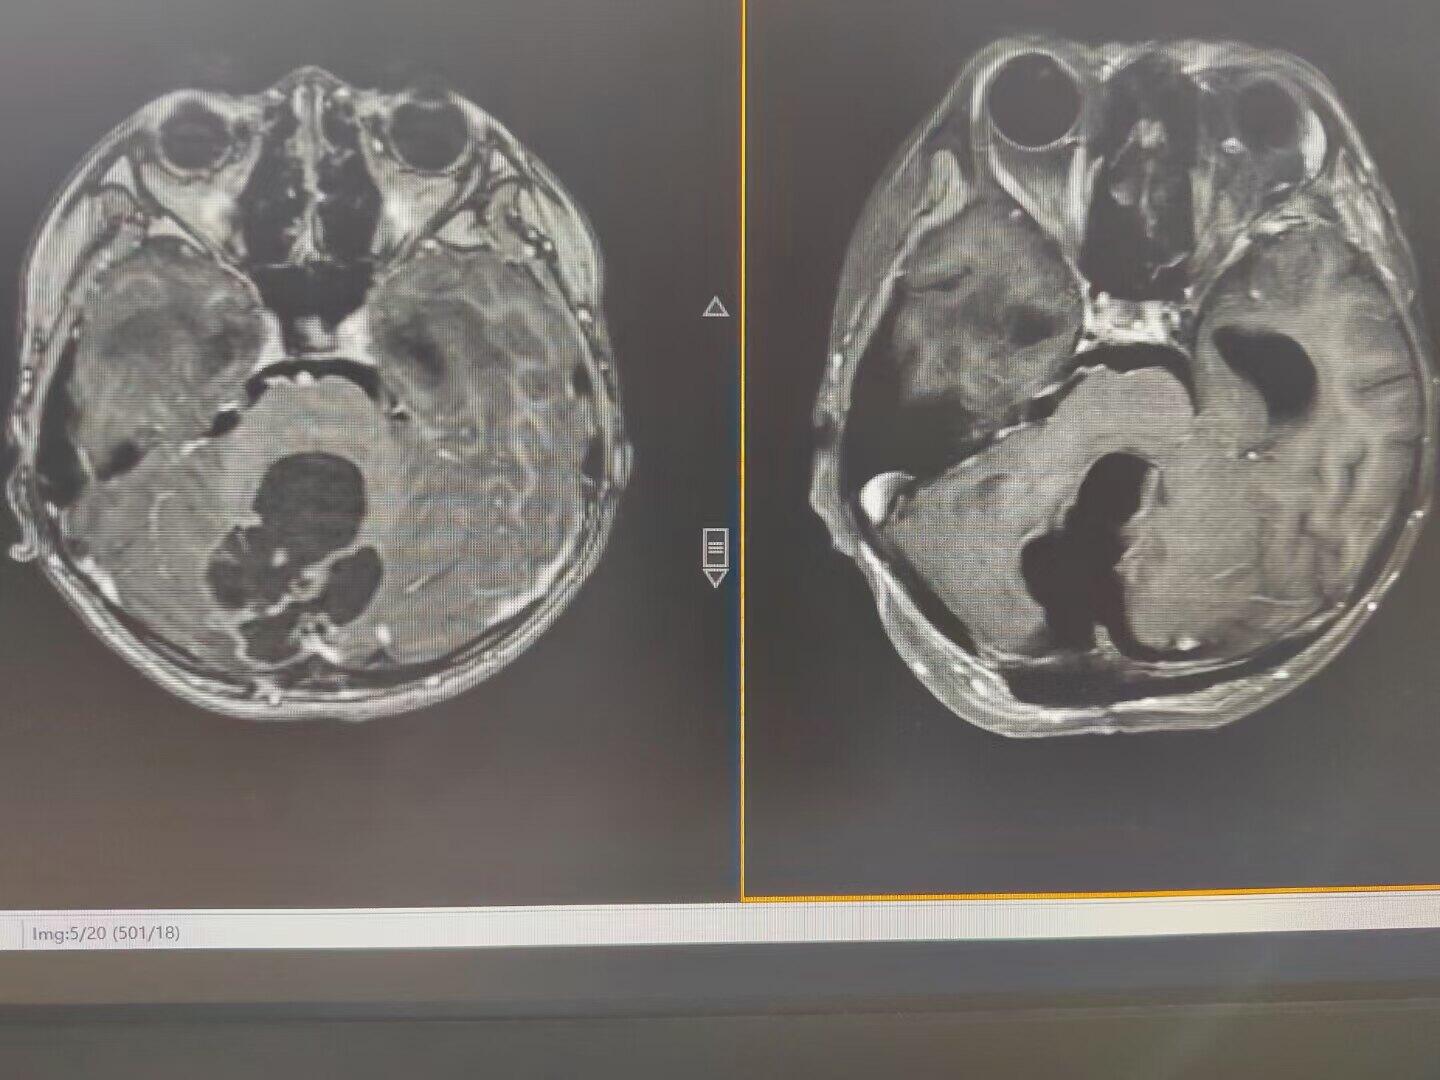

后颅窝占位引起梗阻性脑积水,术前已经出现视力模糊,脑室ommaya测压大于50cm水柱,临时外引流缓解颅压后患儿视力有恢复,后急诊行后颅窝占位切除,术中切除囊性占位、打通中脑导水管、解除脑干压迫,术后脑积水缓解满意,患儿状态良好。